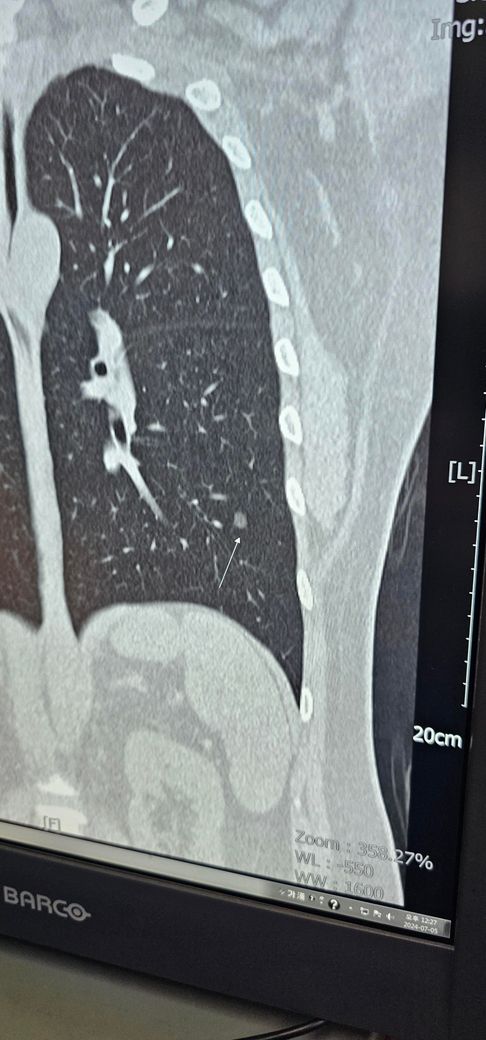

폐ct를 찍었는데 결절인데 모양이나 위치 괜찮은가요

폐ct를 찍어봤는데 결절소견을 들어서

그냥 괜히 걱정이 많이됩니다

35살에 비흡연이지만 가래가자주 생겨서요

위치나모양 괜찮을까요 추적관찰만하면될까요

1년추적 관찰하라구 대충 말하든데

• 1번 째 사진

• 안녕하세요. 신성현 내과 전문의입니다.

모양이 특별히 악성을 시사하는 증거가 있어보이지는 않습니다.

현재 사진만으로는 답변이 어렵습니다. 다만 크기가 크진 않으므로 6-12개월 후 추적검사를 통한 변화 여부 확인이 권고 됩니다.